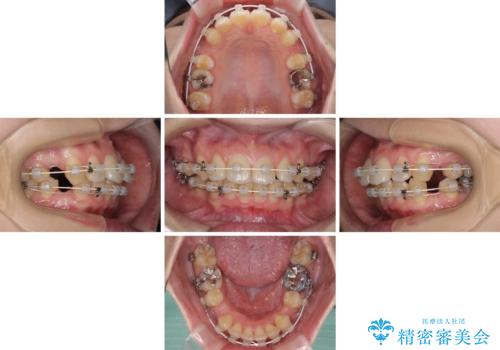

- 審美装置

- 治療期間

- 2年5ヶ月